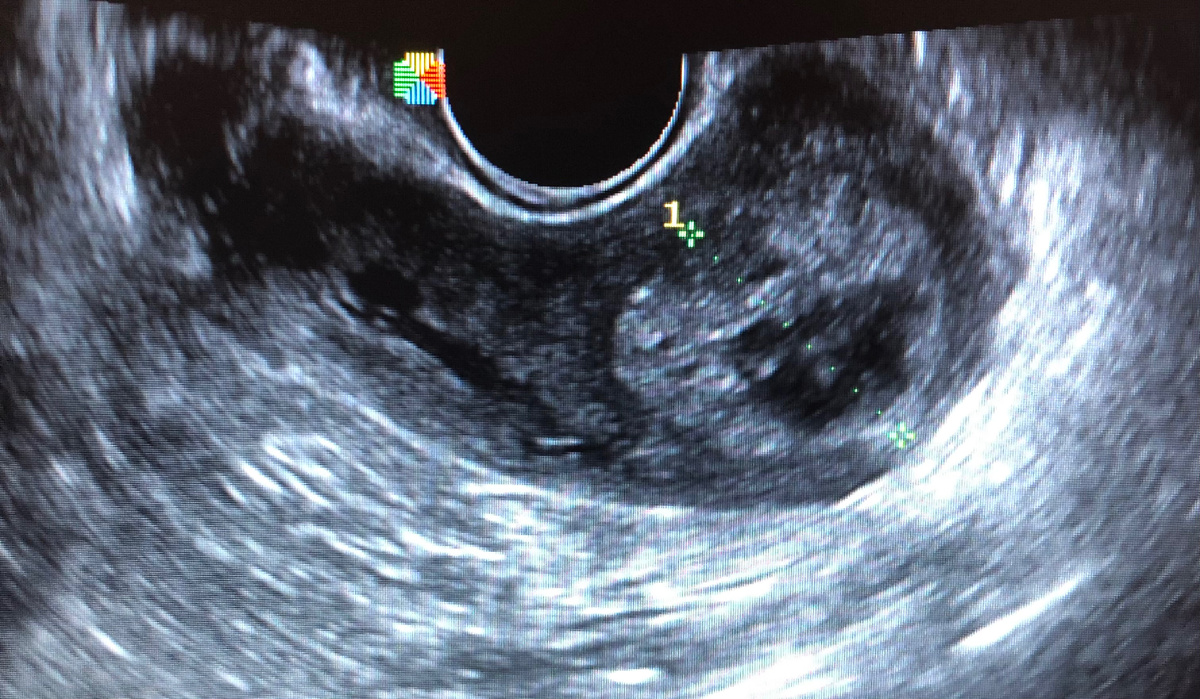

-Тут сгустки крови и остатки тканей…

Эхо-картина остатков плодного яйца после аборта